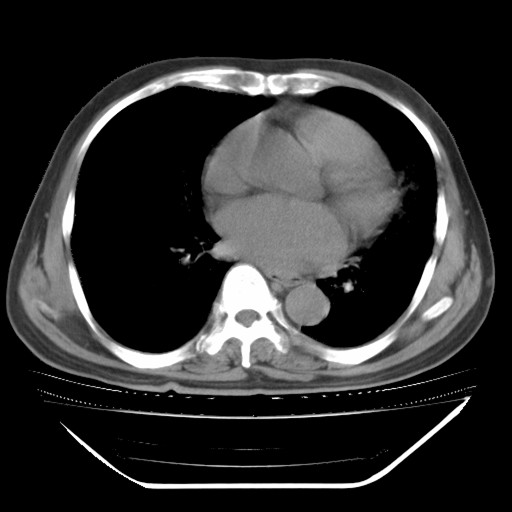

以下是引用hhcckk在2009-5-29 10:34:00的发言:[br]左下肺片絮状边缘模糊影,考虑感染,建议治疗后复查[br]